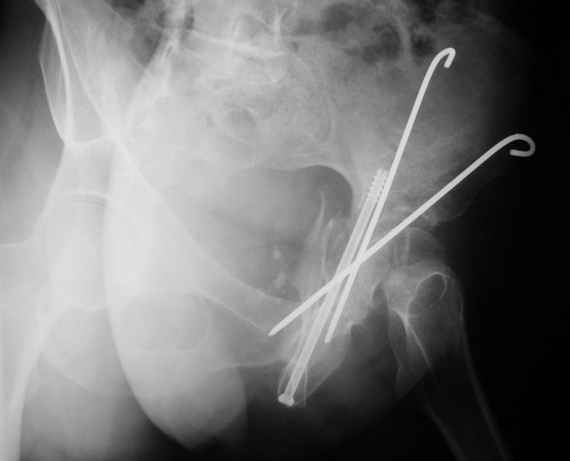

К сожалению, набора для ретроградного или антеградного реконструктивного штифтования в операционной нет, поэтому доставка заняла н-ное время. Вопрос, который возник у меня- по поводу оптимальной тактики хирургии: вся фиксация в один этап из расширенного доступа или последовательно сначала бедро и позже реконструкция впадины, комбинированный доступ к впадине отдельно к передней и задней колоннам или из расширенного илеофеморального одного доступа. Все-таки решил остановиться на одноэтапном подходе и спустя 5 дней (как раз и наборы привезли) из расширенного илеофеморального доступа сначала фиксировал реконструктивным штифтом Smith&Nephews бедро и

шейку (благо перелом шейки 2 типа -относительно стабильный) затем фрагмент крыла подвздошной кости Lag screw, далее пластина на заднюю колонну и винты в переднюю колонну.(с размерами и направлением винтов ошибка вышла:-((, но интраоперационно у меня была полная уверенность , что винты *ушли* в лонную кость).

02.02.04

10.02.04